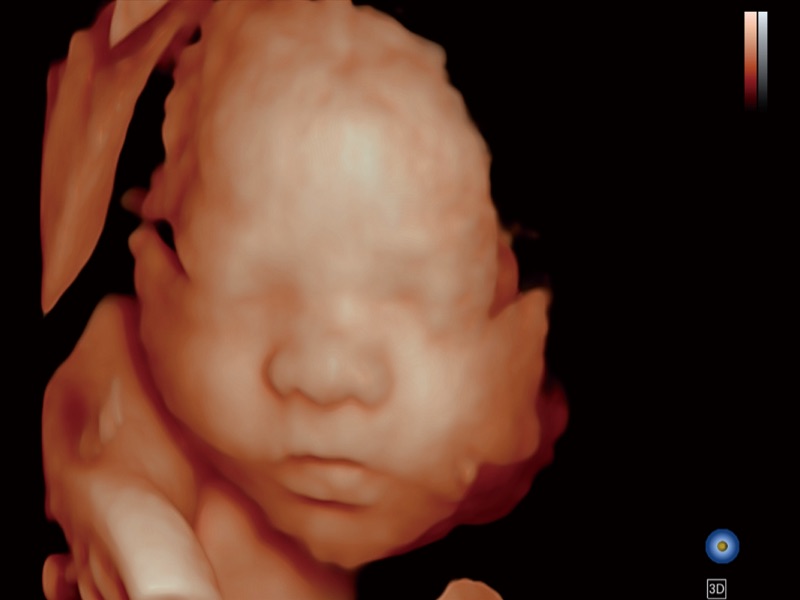

便携式彩色多普勒超声诊断系统

作为开立医疗全新打造的高端全域笔记本超声,X11集成了当前先进的硬件架构和精密的设计工艺,提升多科室临床医生在常规影像检查中的诊断能力,为临床提供全面的诊疗支持。